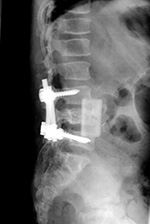

Posterior spinal fusion apparatus |

Shown are pedicle screws and rods on each side, two crosslinks (at L4 and S1), and intervertebral disk spacers at L4-5. |